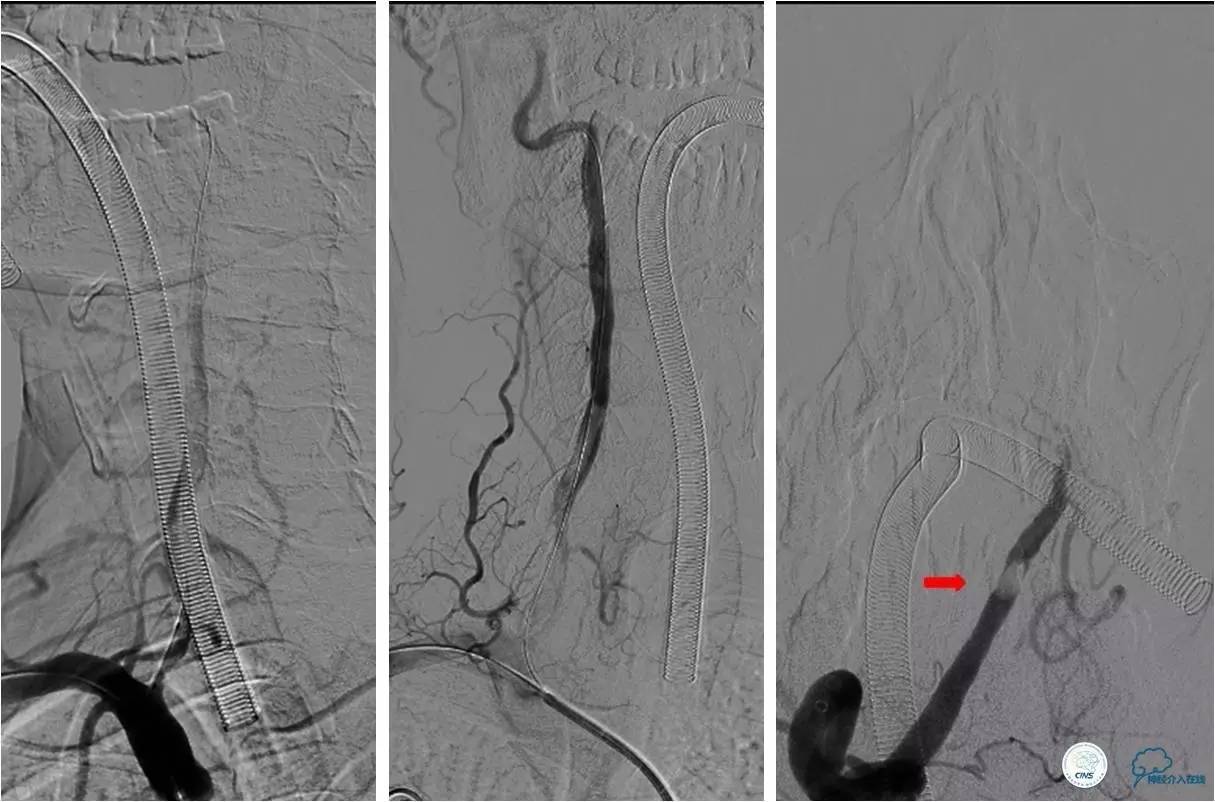

》治疗过程

★2.0x20 mm球囊扩张后,右椎动脉起始段见前向血流,将6F navien颅内支撑导管送至V3段造影,见V4段有血栓,基底动脉闭塞 ;

★Solitaire 6.0x20 mm取栓支架到位造影,取栓两次后基底动脉再通。

★取栓后处理椎动脉起始端的狭窄,椎动脉开口处先放置一枚球扩支架,造影见支架远端仍有狭窄,将Solitaire 6.0x20 mm贴敷在狭窄段,造影见前向血流改善(TICI分级 3级)。